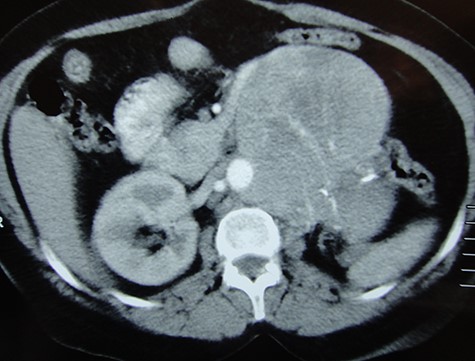

We were encountered with 57-year-old lady complaining of left dull aching loin pain. Examination revealed a palpable mass in the left loin. She gave a history of left RN 15 years ago, and pathology report showed T1b chromophobe RCC (chRCC) with negative resection margin. She was followed for 5 years before being discharged from oncological surveillance. Computed tomography (CT) of the abdomen and pelvis was requested and showed large (13 × 11 × 11 cm3) heterogeneous enhanced mass, occupying left renal bed (Fig. 1). CT of the chest was free of metastases. CT-guided biopsy was done, and pathology was favouring chRCC.

CT scan coronal image showing a large recurrence in left renal bed.